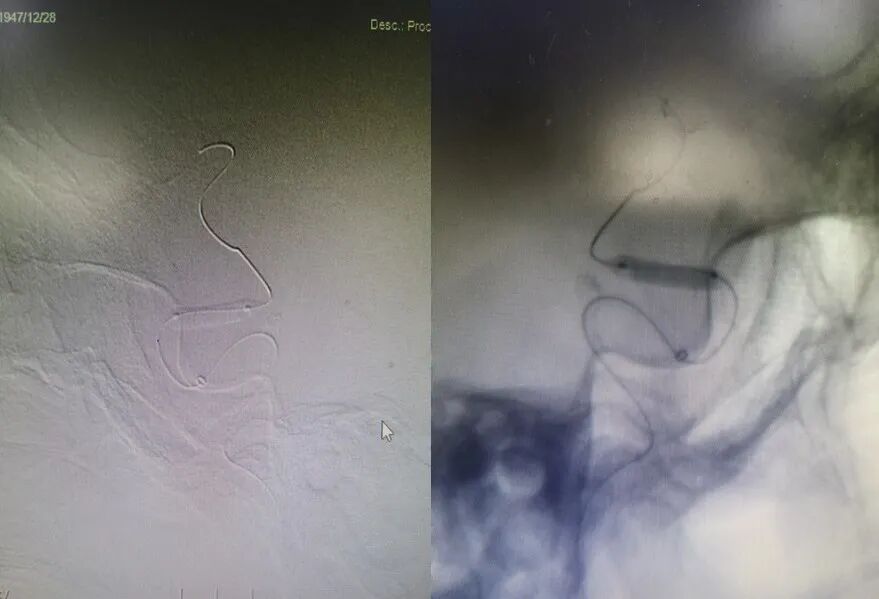

导丝怎么扩【载药时代 球扩天下】NOVA DES®颅内药物洗脱支架在症状性颅内动脉狭窄中的应用—烟台鲁东医院使用体会二例!_https://www.jmylbn.com_新闻资讯_第8张

球囊通过病变,定位准确后扩张,压力8atm,维持30S。

导丝怎么扩【载药时代 球扩天下】NOVA DES®颅内药物洗脱支架在症状性颅内动脉狭窄中的应用—烟台鲁东医院使用体会二例!_https://www.jmylbn.com_新闻资讯_第9张

置入赛诺神畅 NOVA DES®内药物洗脱支架2.5*12mm,压力12atm,维持30S。